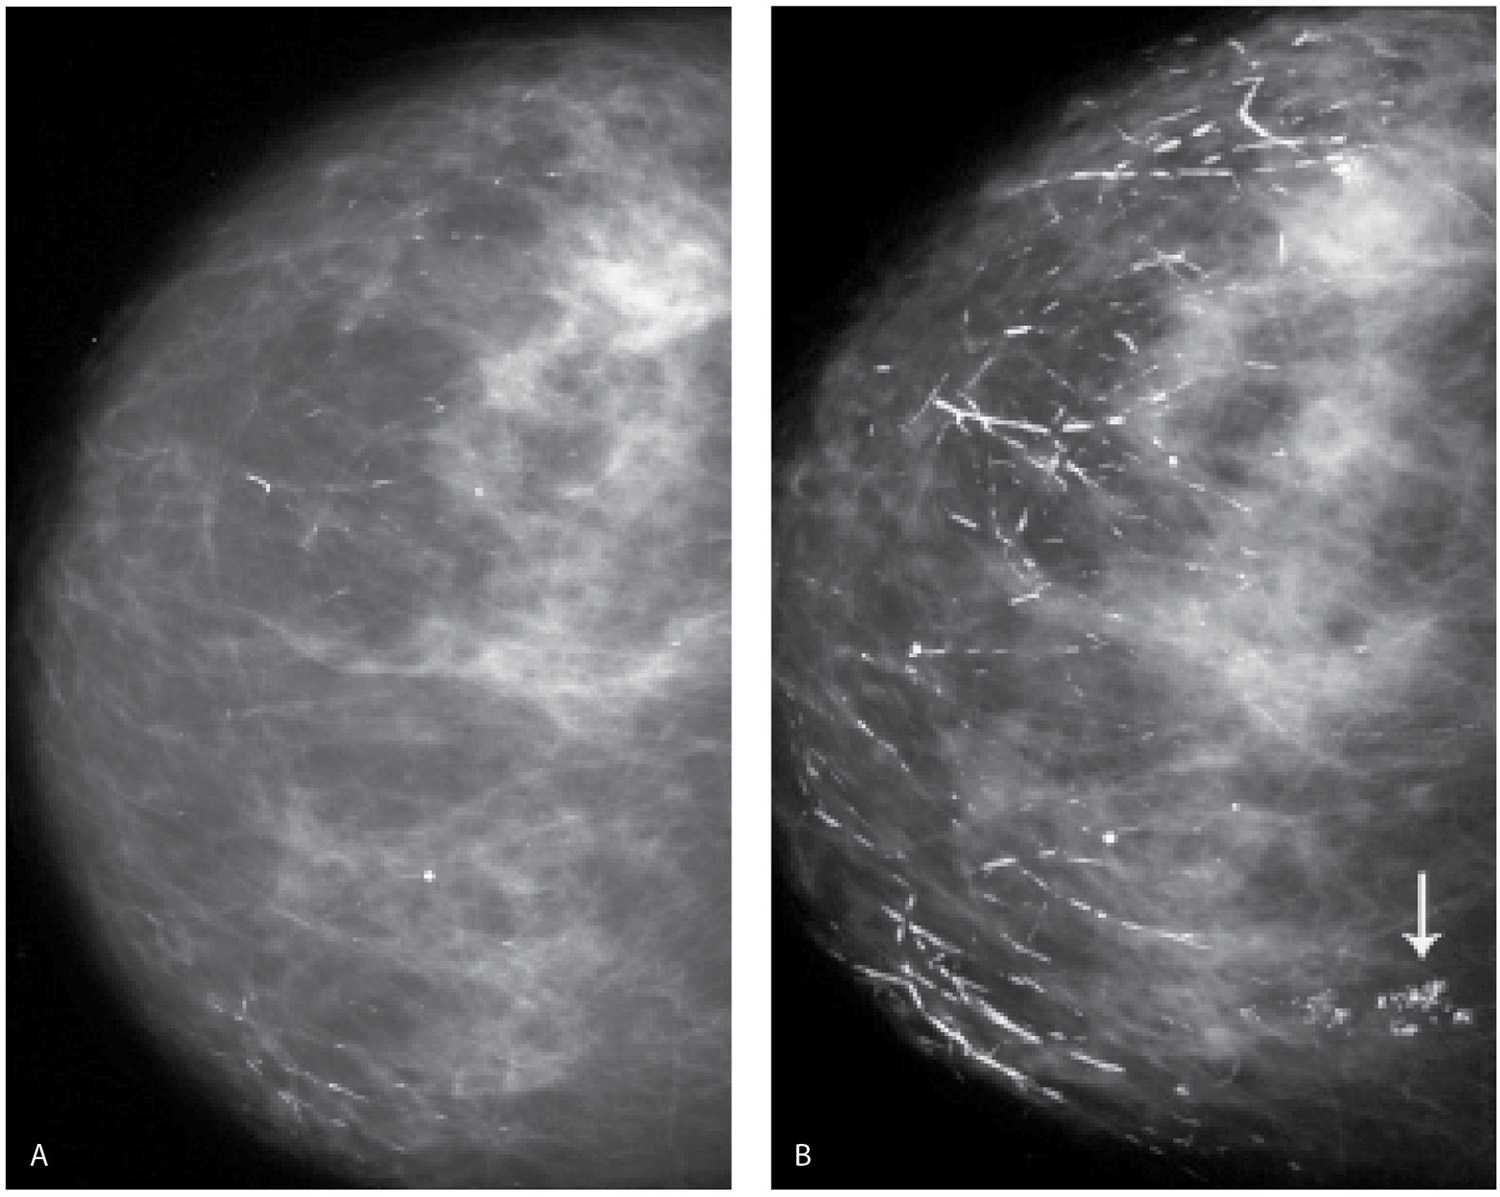

Диагностировать липому может врач хирург после визуального осмотра и пальпации места новообразования. По рекомендации врача может потребоваться УЗИ мягких тканей, маммография или биопсия с цитологическим или гистологическим исследованием.

По рекомендации врача может потребоваться УЗИ мягких тканей, маммография или биопсия с цитологическим или гистологическим исследованием.

Внутрипротоковая папиллома молочной железы

Также относится к доброкачественным новообразованиям, которое располагается в зоне молочных протоков. Она имеет вид нароста размером от нескольких миллиметров до 5-7 см. Папилломы могут быть единичными или множественными, развиваться в одной или в обеих молочных железах.

Причиной развития внутрипротоковая папилломы является нарушение гормонального фона, который могут спровоцировать эндокринные заболевания, стрессы, ожирение, аборты и другое.

Внутрипротоковые папилломы чаще всего развиваются на фоне узловых мастопатий. Протоки молочной железы расширяются, превращаясь в круглые кисты, в которых постепенно разрастаются папилломы. Кровеносные сосуды в области таких папиллом очень ломкие, что и вызывает частые кровоизлияния при любом травмировании молочных желез. Нормальная деятельность клеток нарушена, ткани отмирают, часто развивается некроз.

Основным симптомом заболевания является характерны постоянные выделения из соска — разные по консистенции: прозрачные или кровянистые.

Диагностика внутрипротоковой папилломы:

- осмотр врача-маммолога

- ультразвуковое исследование

- лабораторные исследования выделений из сосков

Дуктография — контрастная рентгенография, дающая возможность выявлять мельчайшие новообразования, их локализацию и оценивать их злокачественность или доброкачественность, а также объем необходимого оперативного вмешательства.